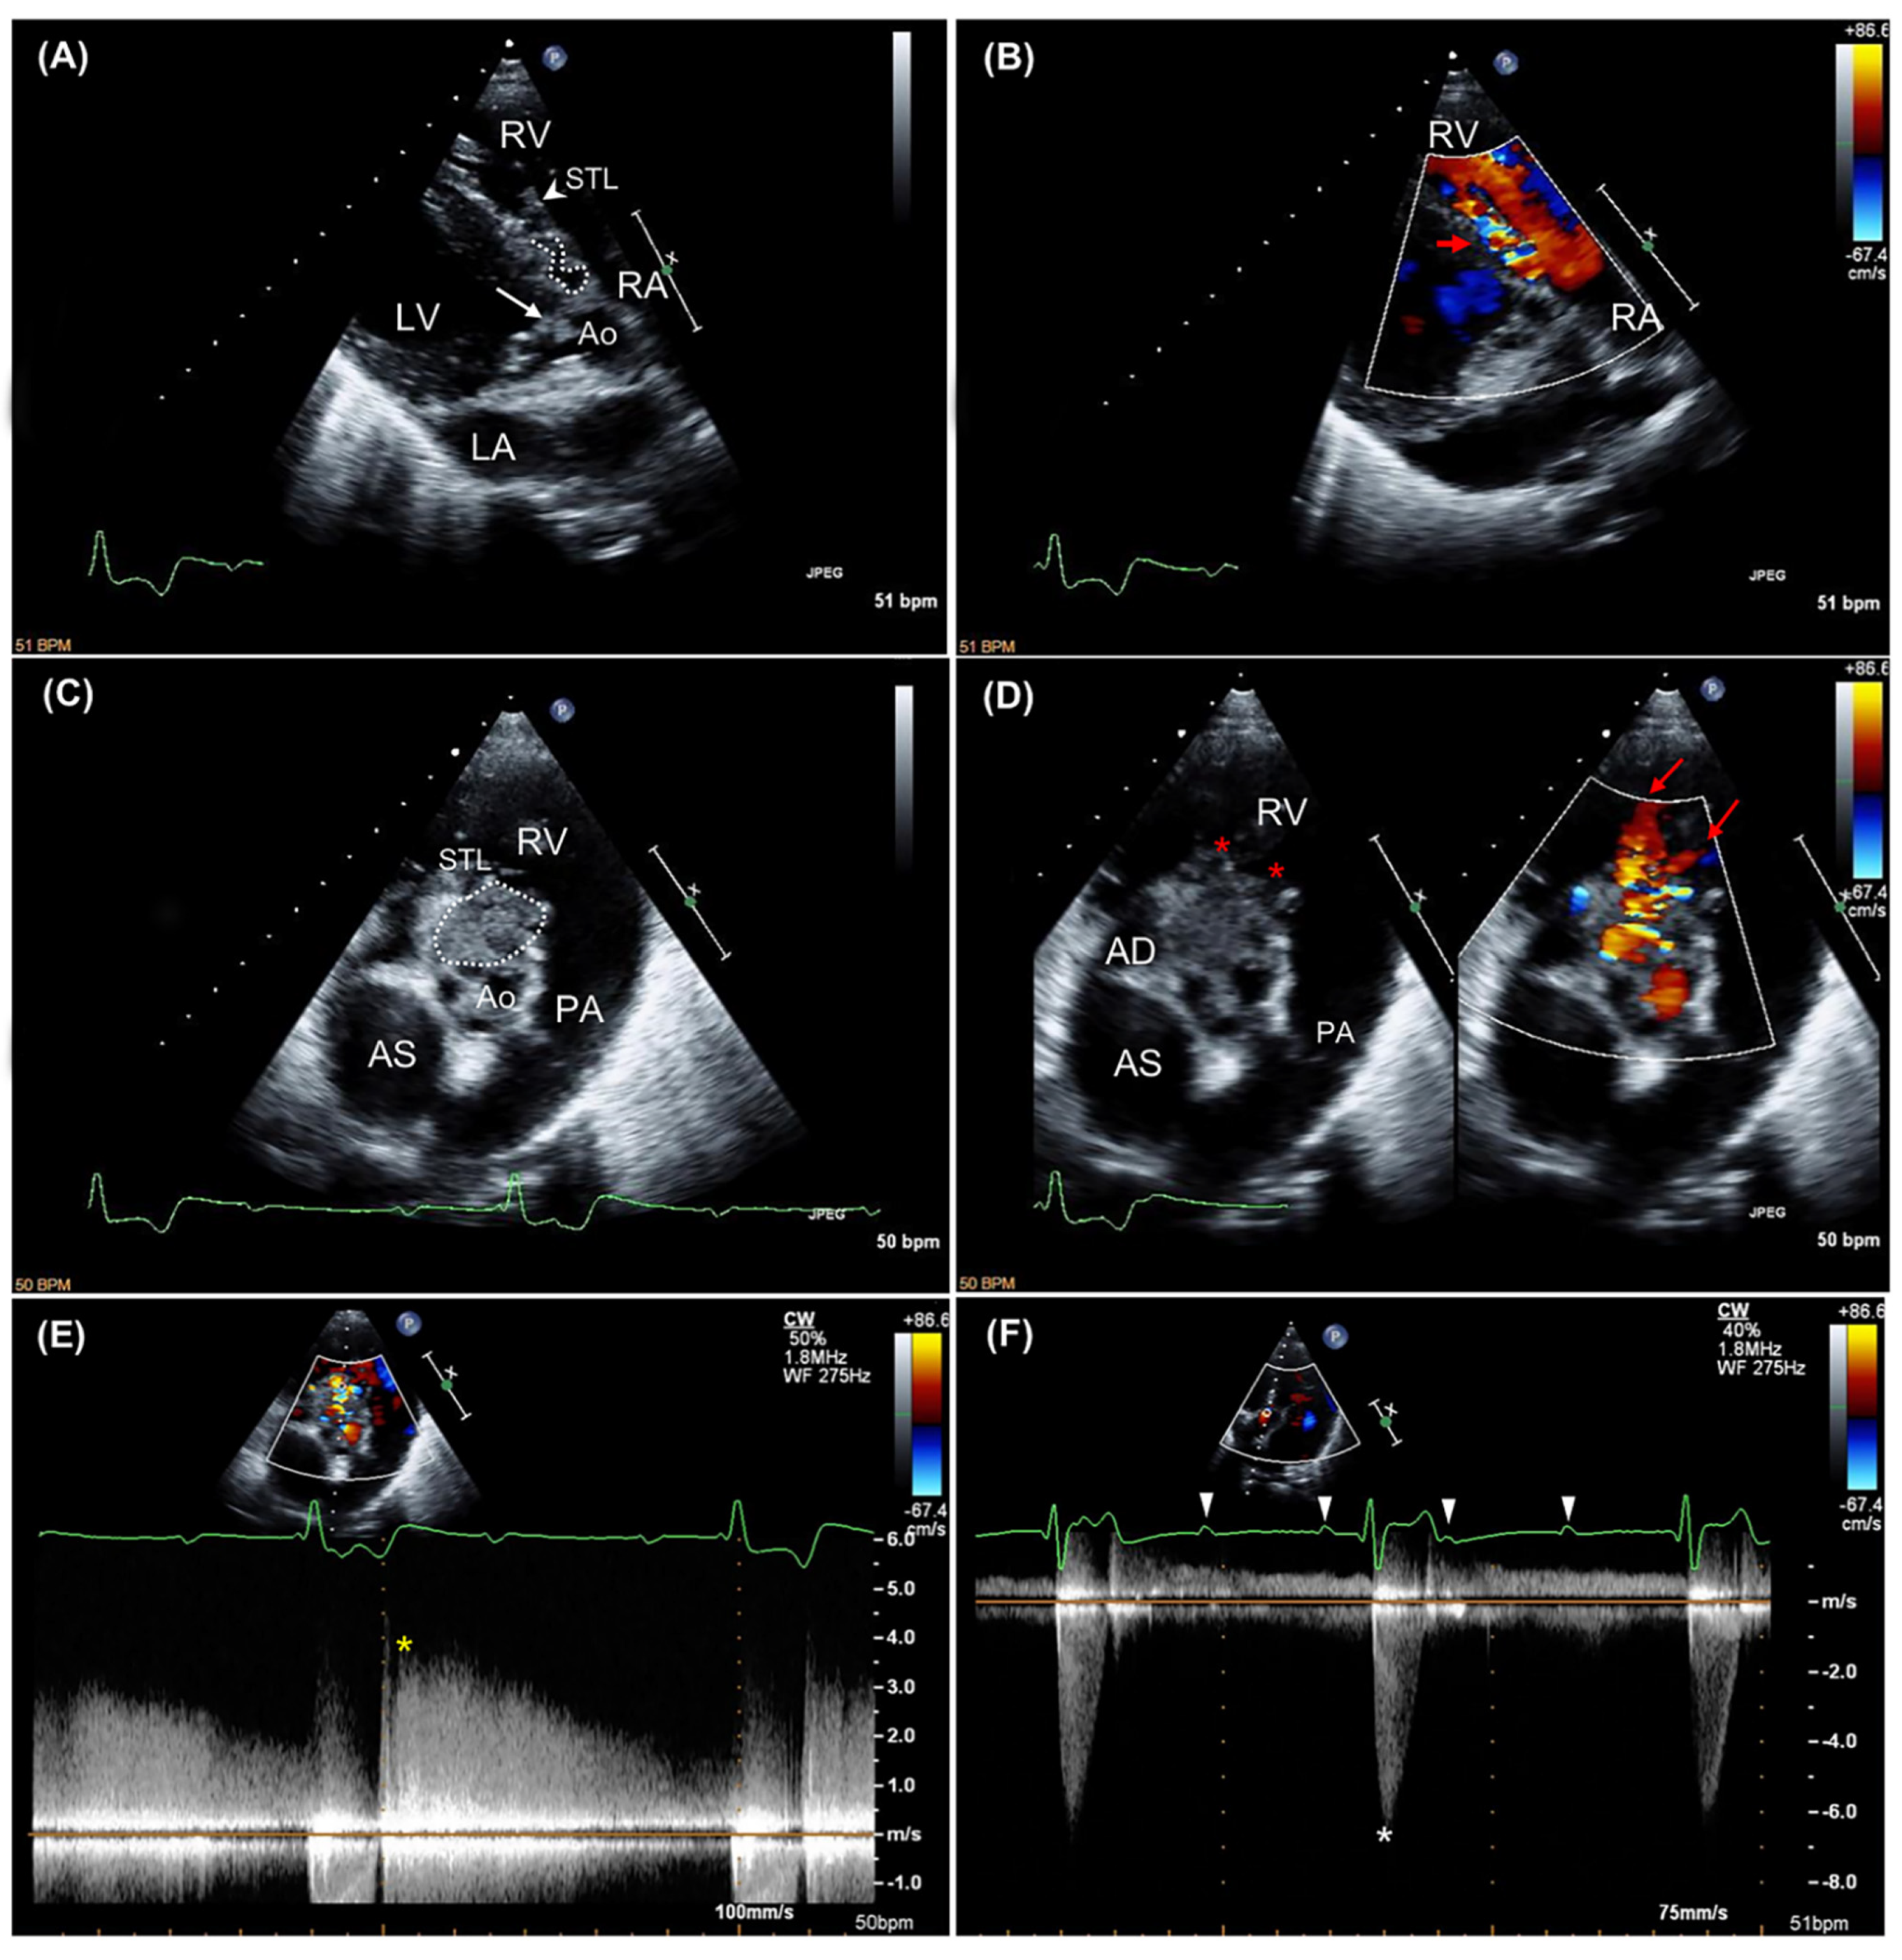

2.1. Case Description and Clinical Investigations